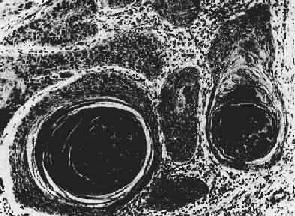

(1)囊腺瘤(cystadenoma):是由于腺瘤组织中的腺体分泌物淤积,腺腔逐渐扩大并互相融合成囊,肉眼上可见大小不等的囊腔,因而得名。囊腺瘤常发生于卵巢,亦偶见于甲状腺及胰腺。卵巢囊腺瘤主要有两种类型:一种为腺上皮向囊腔内呈乳头状生长,并分泌浆液,故称为浆液性乳头状腺瘤(serous papillary cystadenoma);另一种分泌粘液,常为多房性,囊壁多光滑,少有乳头状增生,称为粘液性囊腺瘤(mucinous cystadenoma) (图7-11)。浆液性乳头状囊腺瘤较易发生恶变,转化为浆液性囊腺癌(serous cystadenocarcinoma)。

图7-11 卵巢粘液性囊腺瘤

肿瘤呈多房性囊状,囊腔内含粘液